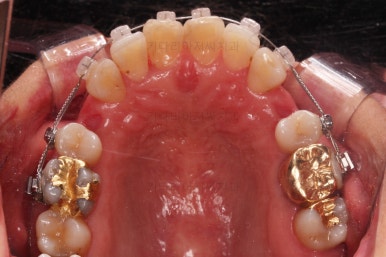

동래임플란트교정 마무리 되었습니다.

임플란트 머리도 잘 올라갔고, 치열도 가지런해졌으며 교합이나 중앙선도 적절히 마무리 되었습니다.

전후 비교를 해보겠습니다.